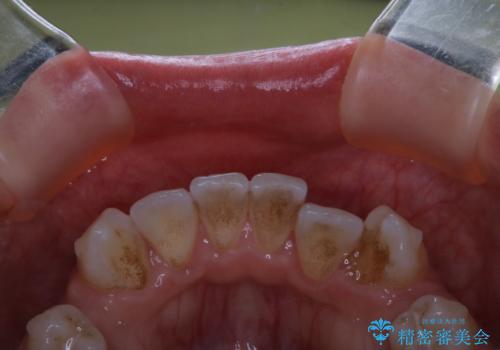

- インビザラインでのマウスピース矯正中に着色が気になるとのことでした。着色が全体的に付着していたためPMTC60分コースを行いました。

プラークが放置されると、そこで歯周病菌が繁殖し始めます。よって歯肉に炎症が生じ、歯周病に引き金となります。

PMTC(保険外治療)は、毎日の歯磨きで落としきれない汚れや、コーヒ、紅茶・タバコのヤニなどの着色も除去します。目には見えない歯と歯の間・歯肉の境目・インビザライン中はアタッチメント周囲などに残っているプラーク(歯垢)もしっかり取り除きます。PMTCでは専門的な機械や材料を使用して、徹底的に汚れを除去するため、虫歯・歯周病・口臭予防などにつながります。